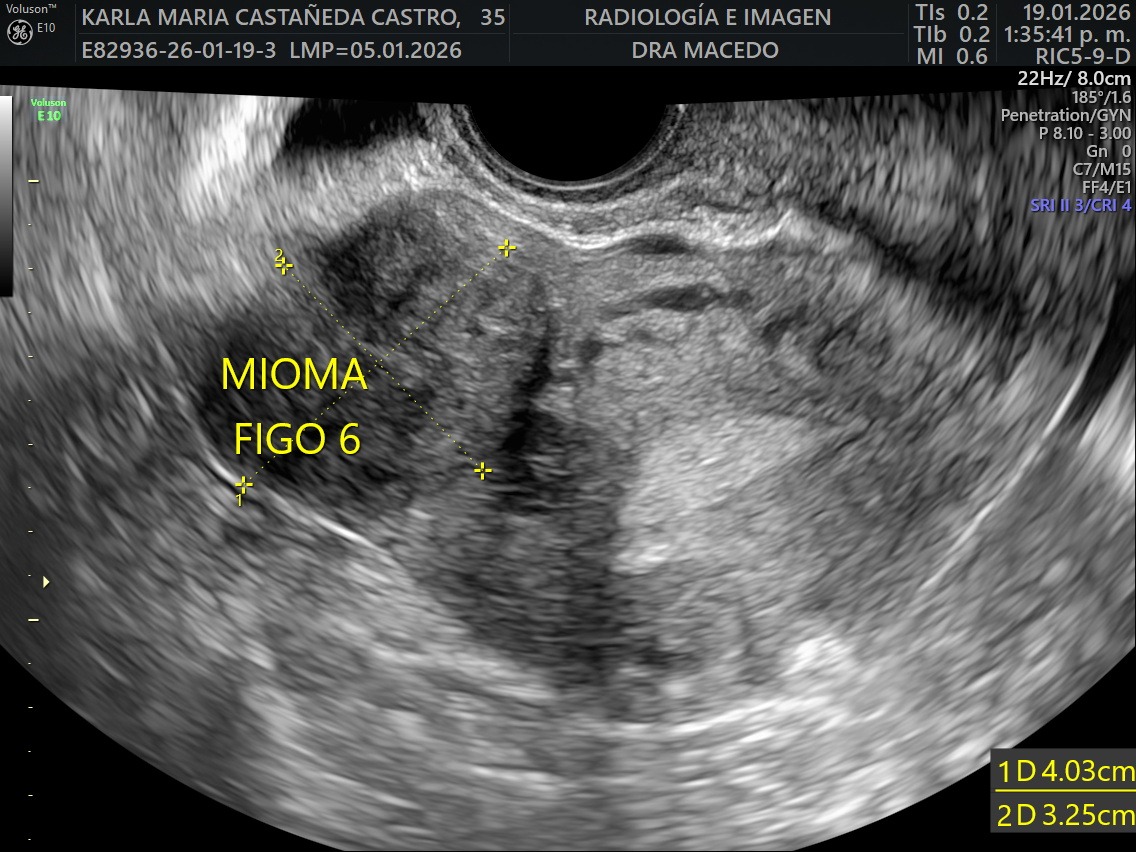

I was recently diagnosed with 16 large uterine fibroid tumors (myomas). My doctors have told me that I need immediate major surgery to remove them. The procedure I will undergo is an Open Abdominal Myomectomy, along with a biopsy to ensure there are no cancerous cells. I will also need to stay in the hospital for approximately five days during recovery. Although even if the tumors are benign, they are putting extreme pressure on my surrounding organs causing significant pain, bleeding, fatigue, and health related issues on a daily basis.

Recientemente me diagnosticaron 16 tumores de fibromas uterinos (miomas). Mis médicos me han informado que necesito una cirugía mayor inmediata. El procedimiento al que me someteré es una miomectomía abdominal abierta, junto con una biopsia para asegurar que no haya células cancerosas. También necesitaré permanecer en el hospital aproximadamente cinco días durante la recuperación. Aunque los tumores de miomas parecen ser benignos, están ejerciendo una presión extrema sobre mis órganos que los rodean, causando dolor significativo, sangrado, fatiga y problemas de salud a diario.